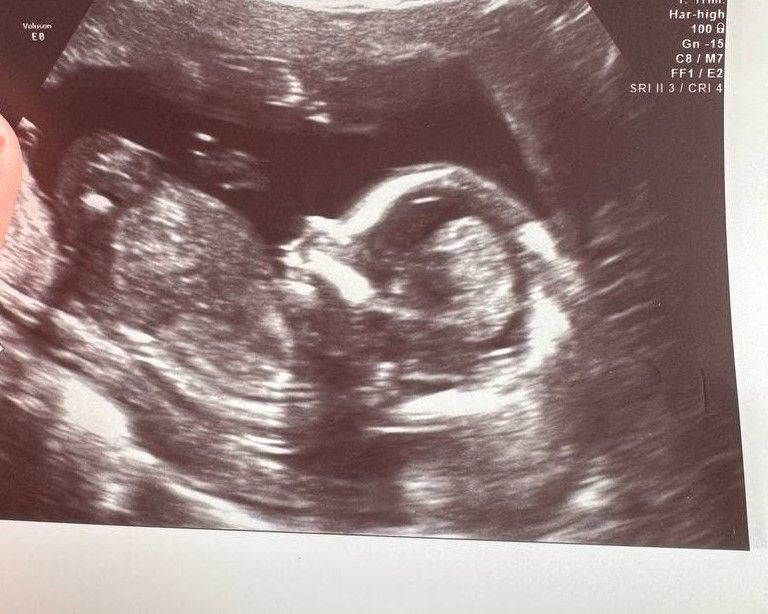

Пол малышаВсем привет! Срок сегодня 15+3. Позавчера решила сходить на узи, посмотреть все ли хорошо с малышом и, возможно, сразу узнать пол:) Хотела красиво преподнести фотографию узи родственникам когда буду рассказывать о беременности)

В общем выяснилось, что у нас будет мальчик😃 Причем там уже точно без сомнений, он специально ножки расставил, и прямо в экран тыкал своим хозяйством, причем еще и со всех ракурсов попой поворачивался, мол :"Смотри, мама, видала какой!!"🤣

С самим малышом все отлично, он опережает срок аж на неделю, по размерам соответствует 16+2 (богатырь какой-то растет по ходу😁), весело играет с пуповиной и любит хвастаться тем, что у него есть)))

Фотография на память: